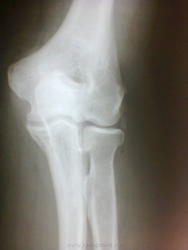

Валентин Львович, на снимках всё это так подозрительно не выглядит, и свежей травмы нет," может быть, когда то давно", ну со слов больного... и то он очень не уверен, а сейчас у него "локоть побаливает и если щупать, раздвоенный какой-то"... так что с ним???

А это (без боковой трудно), по всей видимости, окостенения сумочно-связочных компонентов, как вариант...

Я отметил стрелками "не норму", но эта "ненорма" к артрозу отношения не имеет.

Я так понимаю что "раздвоенный" локтевой отросток локтевой кости. Ну тогда надо снять локоть в аксиальной проеции